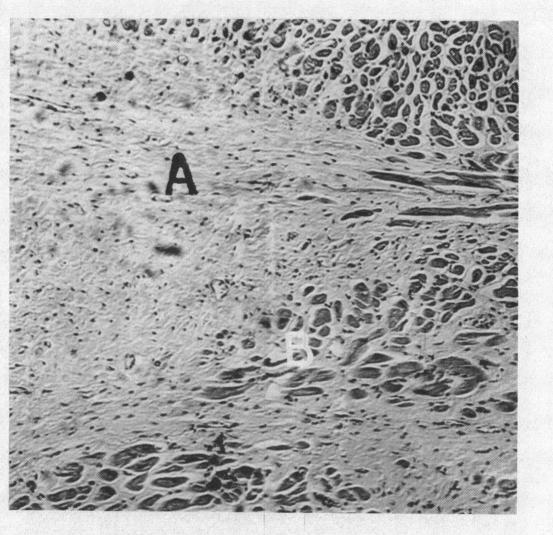

Endomyocardial fibrosis in the Ceylonese.

Br Heart J. 1959 Apr;21(2):167-73. doi: 10.1136/hrt.21.2.167.